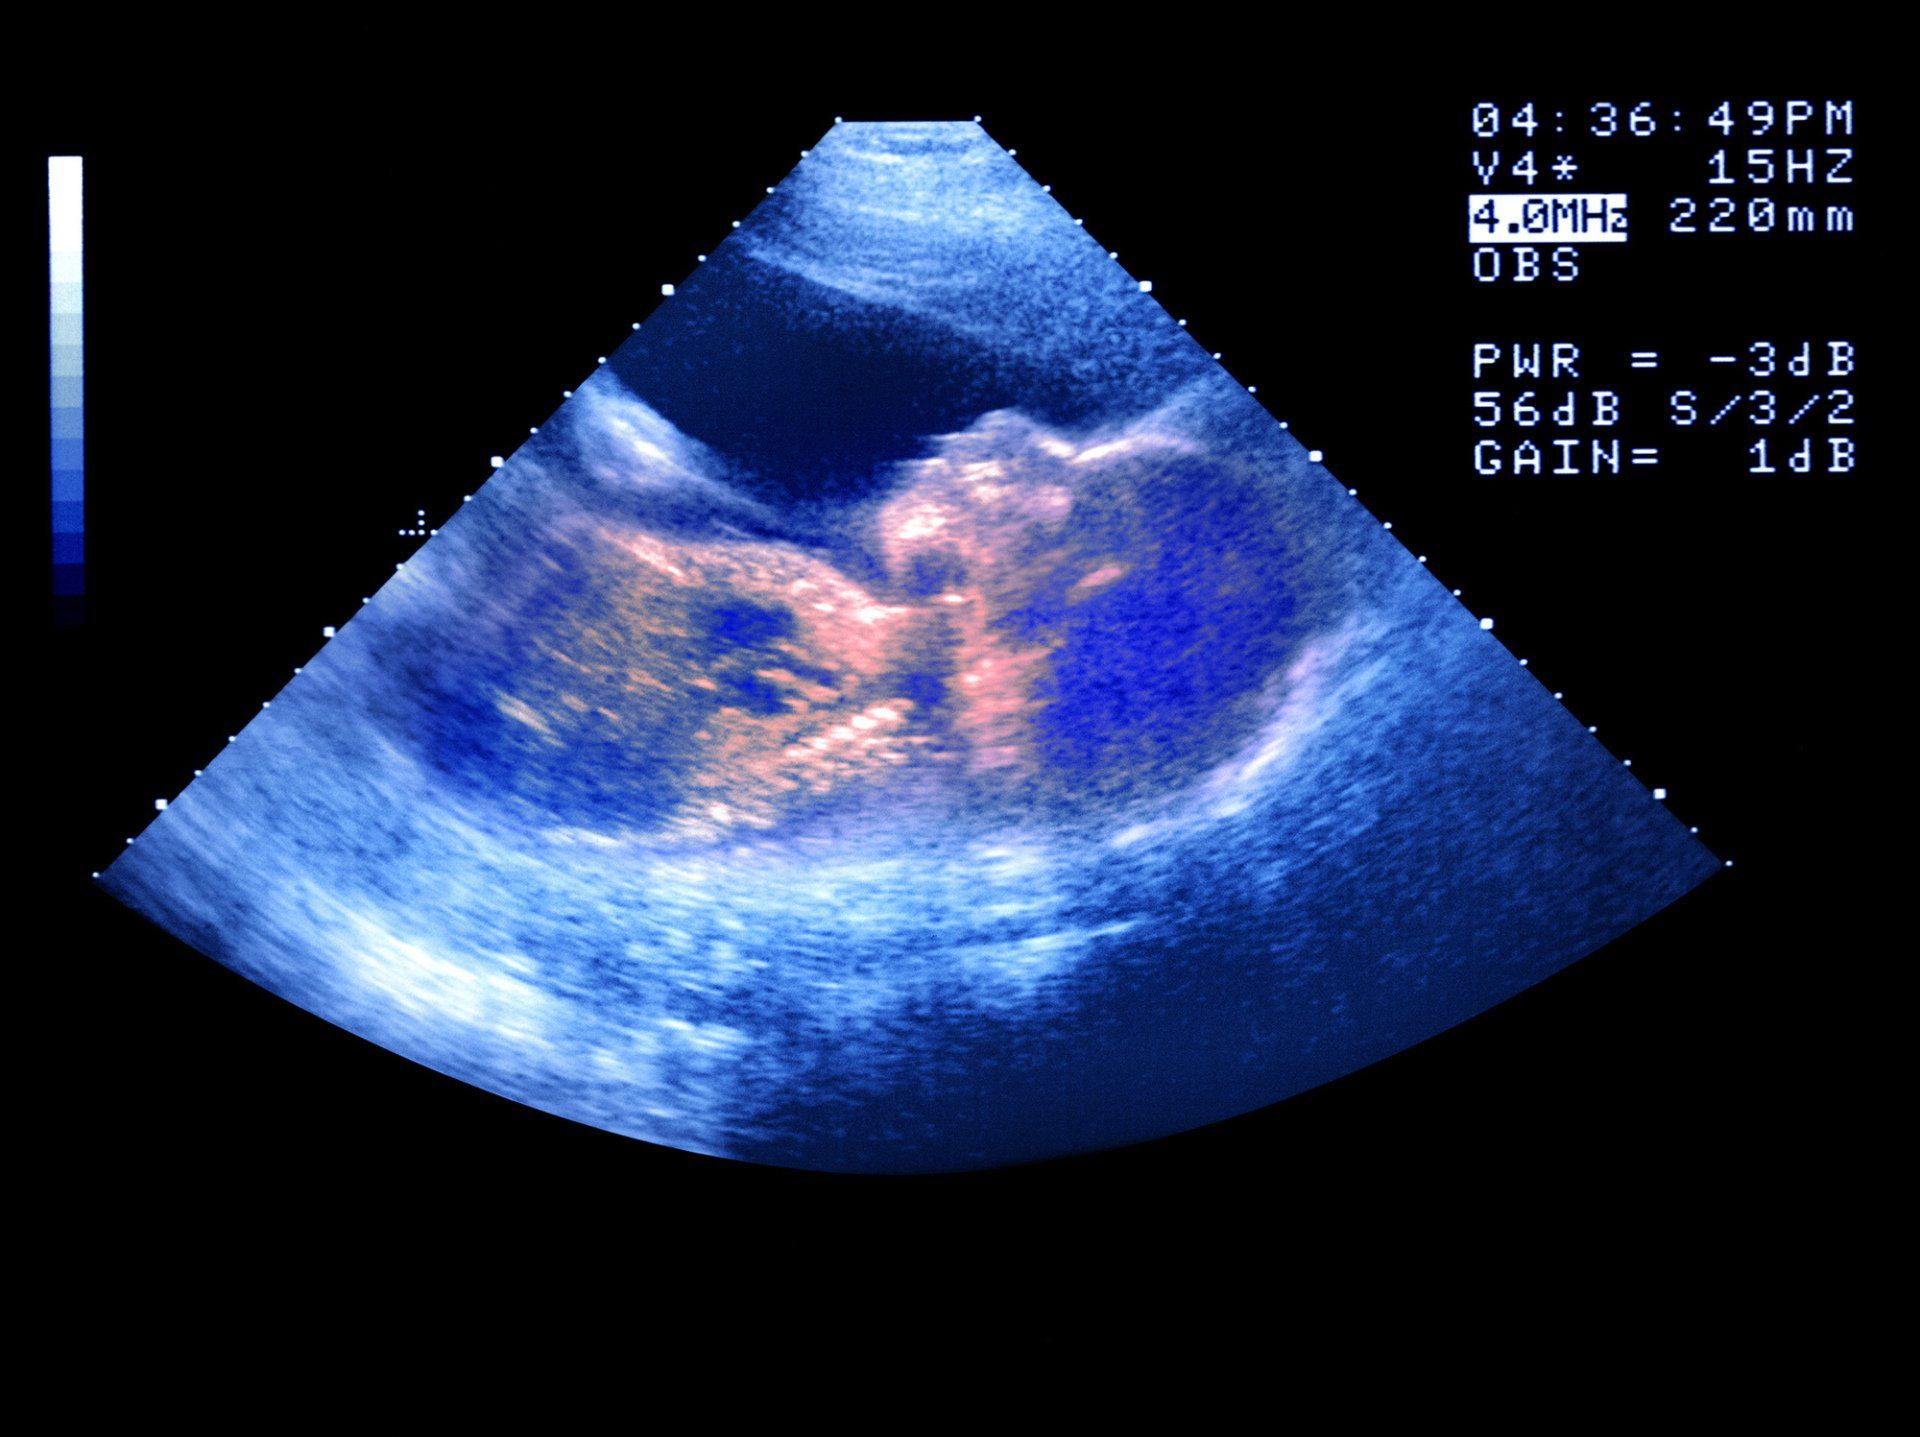

DIAGNOSTICA ECOTOMOGRAFICA

L'ecografia o ecotomografia è un sistema di indagine diagnostica medica che non utilizza radiazioni ionizzanti, ma ultrasuoni e si basa sul principio dell'emissione di eco e della trasmissione delle onde ultrasonore.

Tale metodica viene considerata come esame di base o di filtro rispetto a tecniche di Imaging più complesse come TAC, imaging a risonanza magnetica, angiografia.